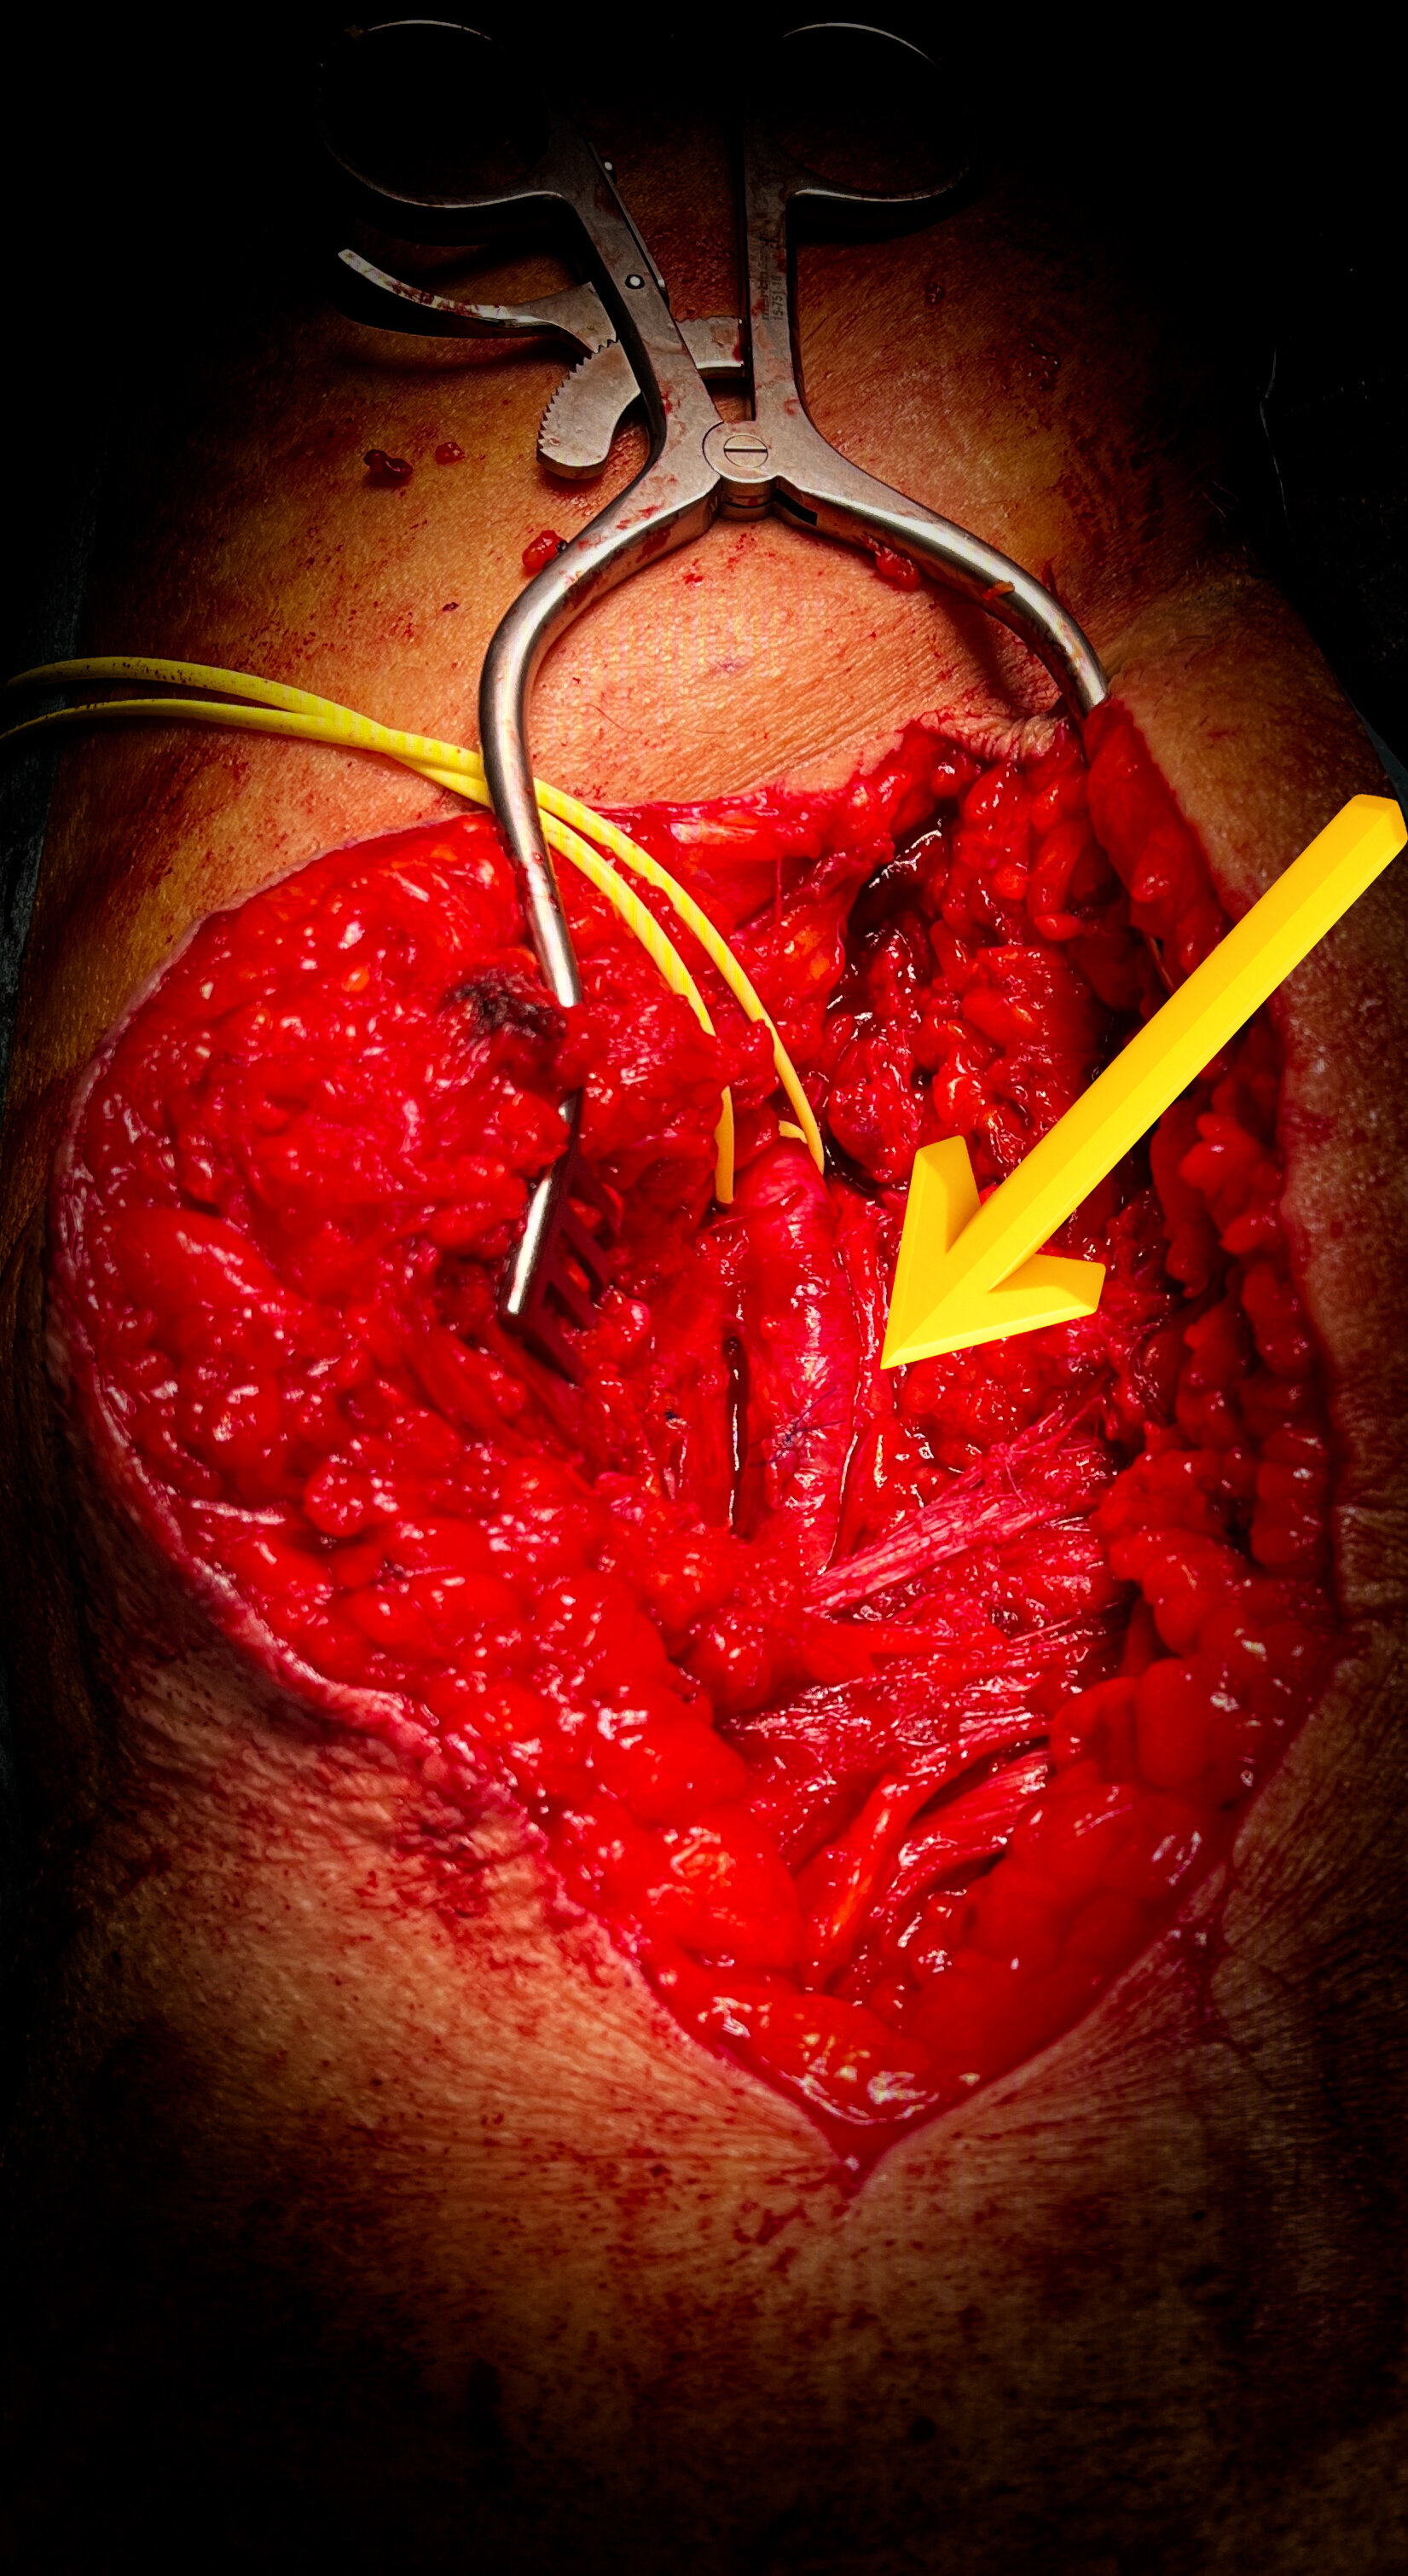

Gli pseudoaneurismi femorali sono i più frequenti. La causa più comune è la deiscenza anastomotica tra una protesi sintetica e l’arteria femorale in seguito a un bypass aorto-femorale o femoro-popliteo. Le complicanze comprendono trombosi, rottura ed embolizzazione distale. Un’altra causa frequente è rappresentata dalle procedure diagnostiche e terapeutiche interventistiche che implicano il cateterismo dell’arteria femorale.